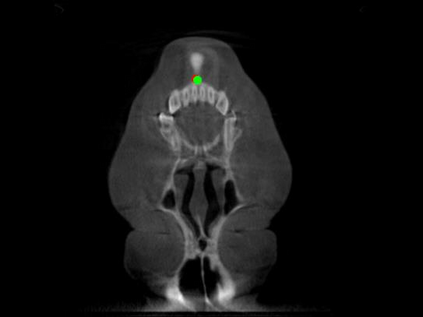

Detecting 3D landmarks on cone-beam computed tomography (CBCT) is crucial to assessing and quantifying the anatomical abnormalities in 3D cephalometric analysis. However, the current methods are time-consuming and suffer from large biases in landmark localization, leading to unreliable diagnosis results. In this work, we propose a novel Structure-Aware Long Short-Term Memory framework (SA-LSTM) for efficient and accurate 3D landmark detection. To reduce the computational burden, SA-LSTM is designed in two stages. It first locates the coarse landmarks via heatmap regression on a down-sampled CBCT volume and then progressively refines landmarks by attentive offset regression using multi-resolution cropped patches. To boost accuracy, SA-LSTM captures global-local dependence among the cropping patches via self-attention. Specifically, a novel graph attention module implicitly encodes the landmark's global structure to rationalize the predicted position. Moreover, a novel attention-gated module recursively filters irrelevant local features and maintains high-confident local predictions for aggregating the final result. Experiments conducted on an in-house dataset and a public dataset show that our method outperforms state-of-the-art methods, achieving 1.64 mm and 2.37 mm average errors, respectively. Furthermore, our method is very efficient, taking only 0.5 seconds for inferring the whole CBCT volume of resolution 768$\times$768$\times$576.